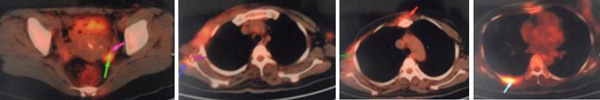

In June to August 2011, KT went to China for treatment. PET/CT scan showed the wound was 14 x 12 cm and the cancer had spread to her lymph nodes, lungs and bone. This was a Stage 4 cancer.